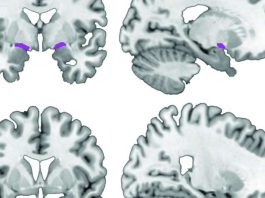

Ученые обнаружили новый регион головного мозга

Мозг, без сомнения, является наименее изученным и наиболее сложным в плане анализа органом человеческого тела – впрочем...